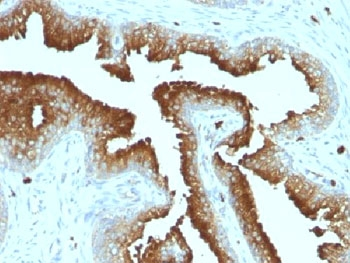

CD63 Antibody / LAMP-3 [orb2637613]

FACS, IF, IHC-P, WB

Human, Mouse

Mouse

Monoclonal

Unconjugated

100 μg